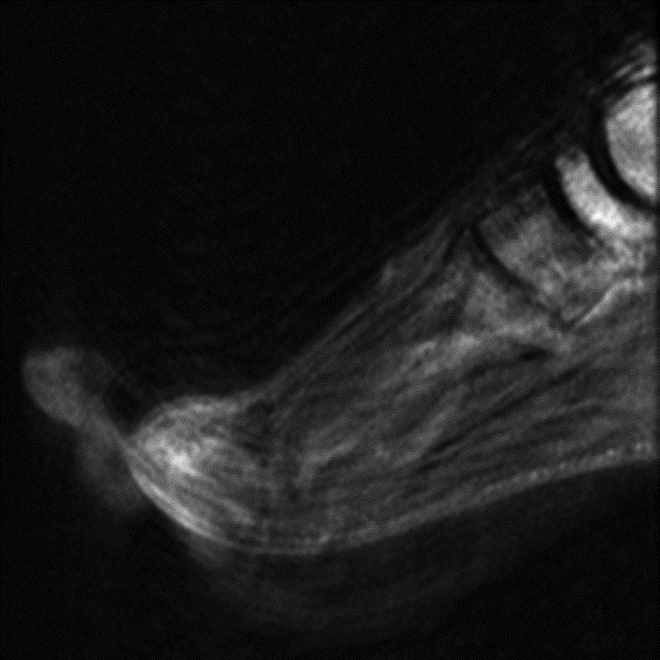

Shading Artifact. (A) Incomplete coil coverage results in dark signal obscuring the soft tissues adjacent to the olecranon at the periphery of sagittal STIR image of the forearm in a patient with cellulitis and concern for abscess. (B) Axial T1-weighted post-contrast fat-saturated image obtained following coil repositioning demonstrates abscess (arrow) in the previously obscured region.